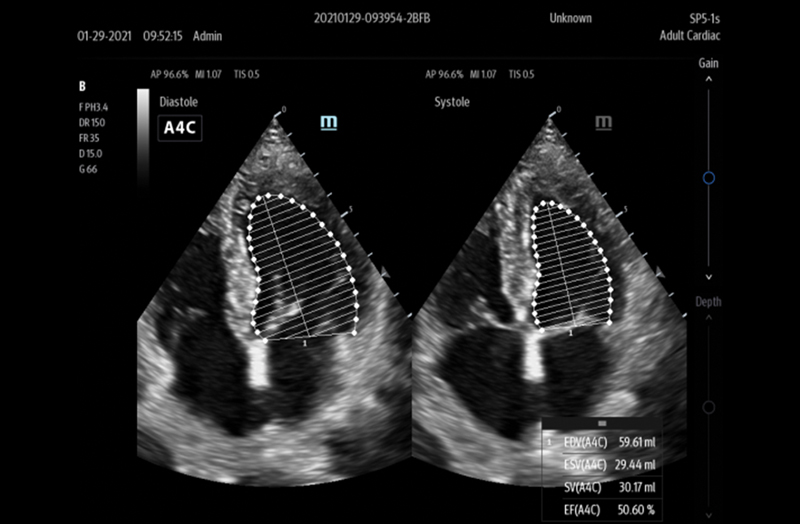

The TE7 Max Ultrasound System is designed to maximize your capabilities in demanding Point of Care environments. With its thoughtful industrial design and best-in-class image quality, the

TE7 Max provides a superior user experience during rapid clinical assessments and procedures taking place at the patient’s bedside

The TE7 Max boasts a large 21.5” vertically oriented high-definition display and a sealed touch-based interface to optimize visualization and accessibility when every second counts. The TE7 Max also incorporates a comprehensive suite of artificial intelligence (AI) powered Smart Tools and workflow enhancement software (iWorks™ Protocol) making efficiency and reproducibility the expectation for all end users.